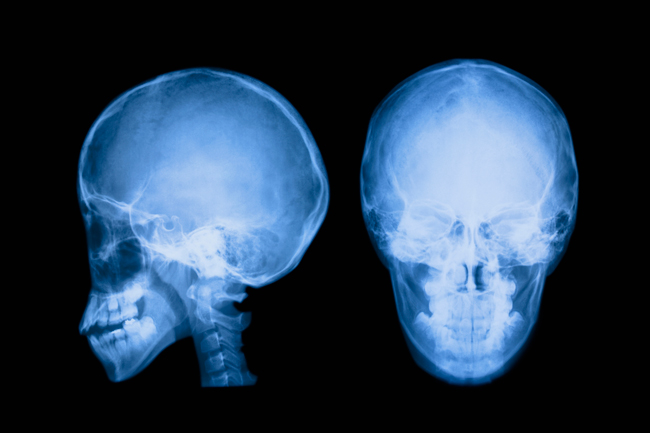

磁気共鳴画像法 (MRI)やコンピューター断層撮影法 (CT)などの検査は、より正確な診断につながる可能性があります。

MRI は、電波と磁場を使用して臓器の画像を生成します。 CT スキャンでは、複数の X 線を使用して、体内の骨や軟構造の断面写真を作成します。